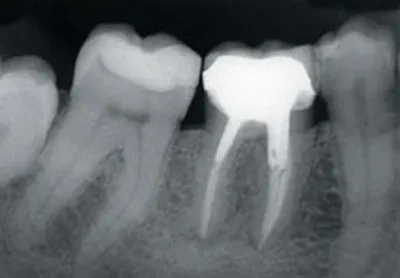

1-1a Preoperative periapical radiograph of a mandibular molar requiring endodontic retreatment prior to placement of a new crown.

1-1b Periapical radiograph taken 9 years postoperatively. Good preparation and irrigation of the canal in conjunction with a good coronal seal ensures the longevity of the treatment.